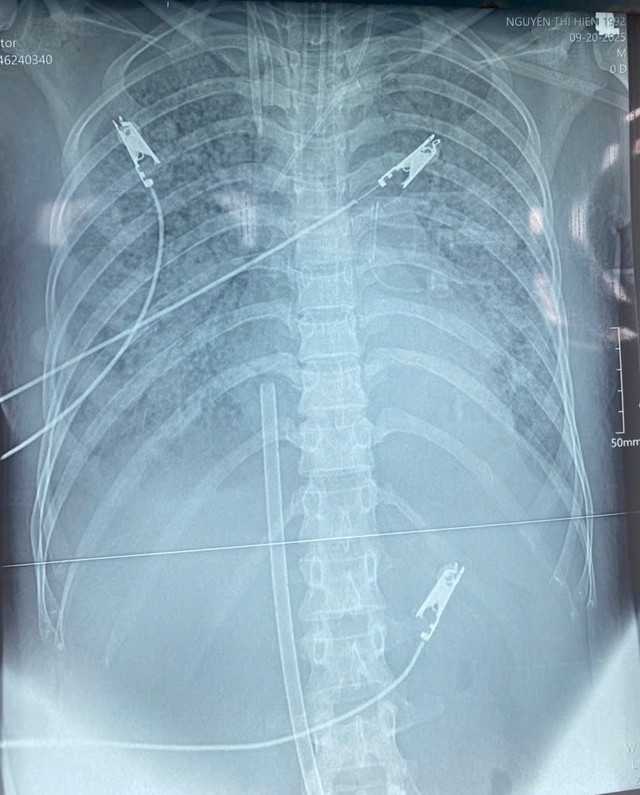

Hình ảnh tổn thương phổi lan toả do nhiễm khuẩn huyết tụ cầu vàng.